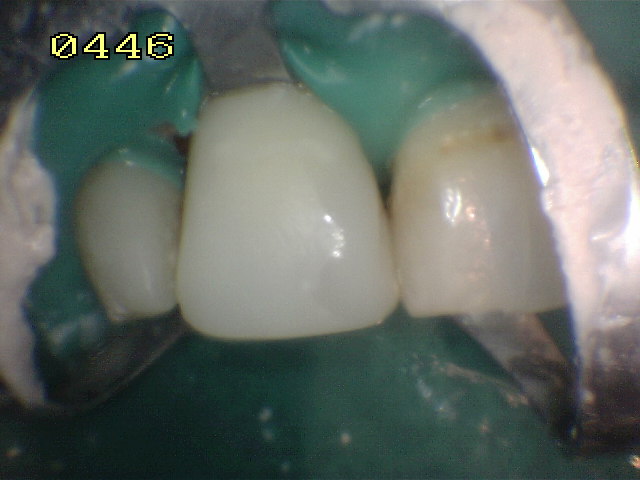

Conformación de la

corona con tiras de celuloide y pulido con discos de papael

y fresas multifilos |

Pulido con pasta

Dentbrill y brochita |